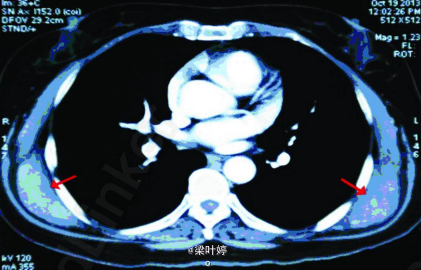

查体:双侧肩胛下角区域可扪及一直径约5cm 硬质类圆形包块,固定。余无特殊。 CT提示:双侧背阔肌及前锯肌深面对称性病变,增强后不均匀强化,周围脂肪间隙清楚。 MRI示::双侧对称性病变,位于背阔肌及前锯肌深面,增强后斑片状强化,周围脂肪间隙清晰,局部与肋骨骨膜关系紧密。